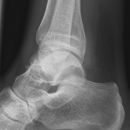

Totale Talusluxation

Talus Fraktur

Snowboard fracture Talus